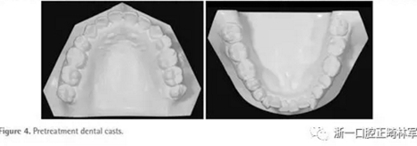

面部照片顯示,患者為凸面型,鼻唇時頦肌緊張(Figure 3)。口內(nèi)檢查顯示雙側(cè)第二前磨牙間開合(Figures3 and 4)。覆合覆蓋分別為-3.5mm和+1.2mm。正面觀,上下牙列中線與面部中線一致。雙側(cè)磨牙II類關(guān)系,下前牙區(qū)中度擁擠。

全景片顯示四顆智齒都存在,上頜切牙有牙根吸收,并且在雙側(cè)髁突都有相當(dāng)大的吸收(Figures 1B and 5A)。頭測分析顯示:ANB angle, 4.5°; FMA, 46.7°; U1-SN, 95.8°; L1-MP, 83.7°(Table 1, Figure 5B)。

基于上述檢查結(jié)果,患者被診斷為雙側(cè)髁突形態(tài)改變引起的開合畸形。